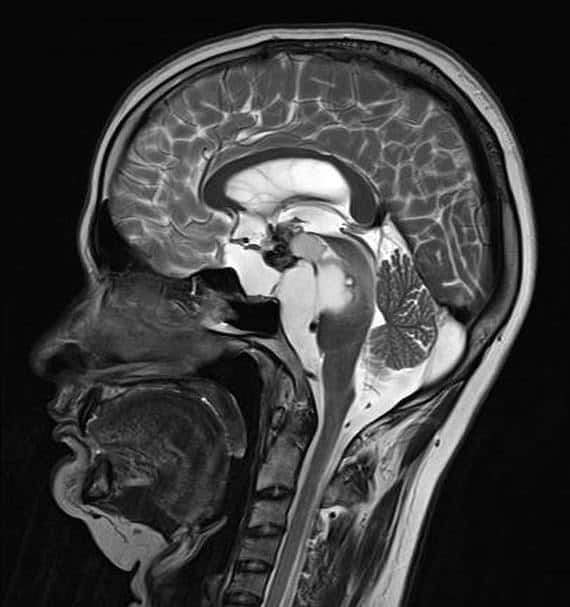

U sọ hầu

» Thông tin: Nam giới – 30 tuổi.

» Lâm sàng: Đau đầu.